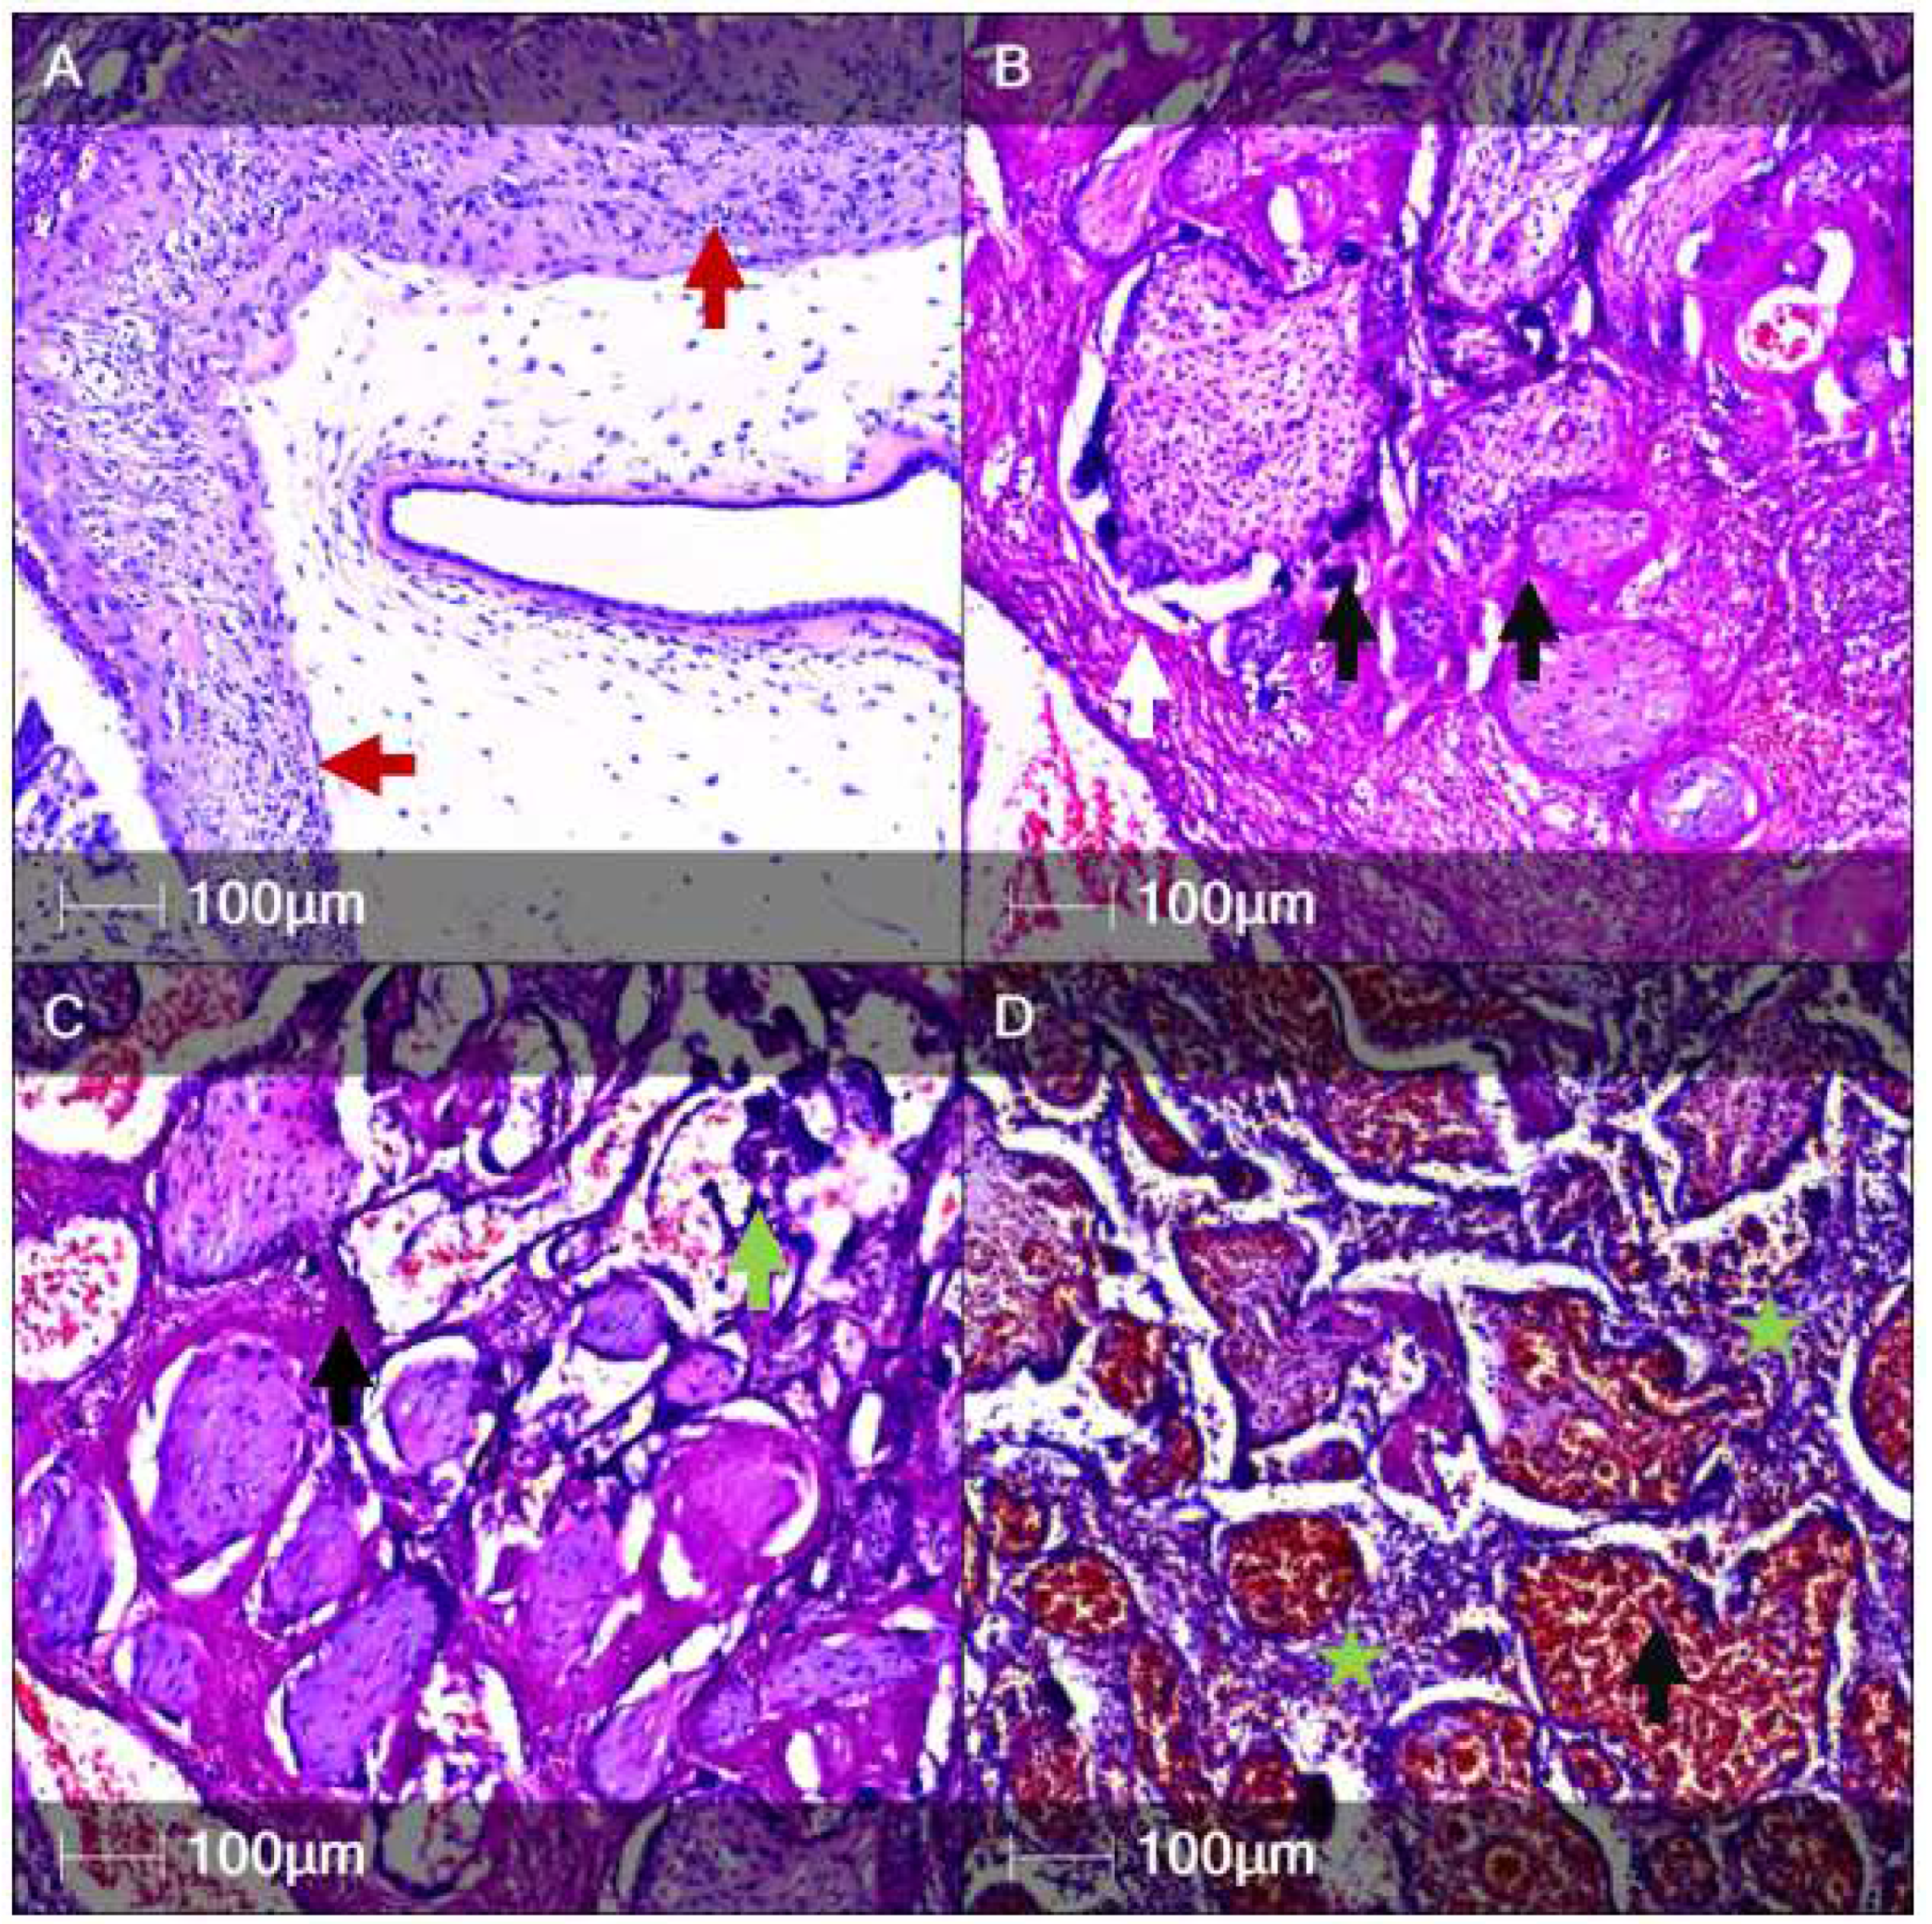

One of our main focus points was examination of the placenta. The placental weight was 50 g, with measurements 12.5 × 8 × 2 cm. Histological examination via hematoxylin and eosin (H&E) staining revealed acute chorioamnionitis (Figure 1A), acute subamnionic placentitis (Figure 1B), multiple intervillous thrombi, chronic deciduitis, perivillous fibrin deposition with syncytiotrophoblast necrosis (Figure 1C), chronic intervillositis and villitis with signs of inflammatory activity (presence of neutrophils), and villous hyperaemia and haemorrhages (Figure 1D).

Figure 1.

Histological examination of the placenta (H&E staining). The panel depicts various components and pathological features of the placenta. (A) Acute chorioamnionitis with signs of necrosis and leukocytoclasis (red arrows); (B) Subamniotic placentitis with intervillous thrombi (white arrow) and necrotic syncytiotrophoblasts (black arrows); (C) Syncytiotrophoblast necrosis (dark blue, green arrow) and intevillous cell debris (black arrow); (D) Subamniotic placentitis with predominantly intervillous neutrophil infiltrates (intervillositis—green asterisk) and severe intravillous congestion and haemorrhages (black arrow).